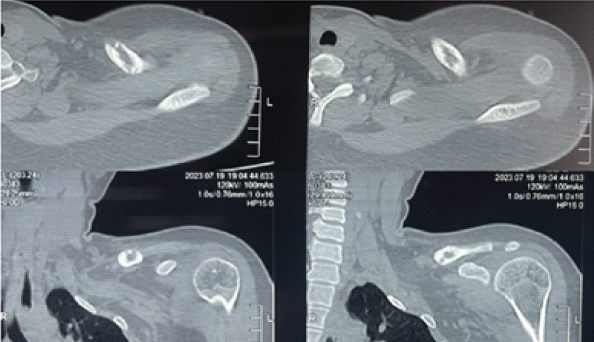

Computed tomography scans were consistent with features of “giant cell tumor” and magnetic resonance imaging reported the possibility of “metastasis” or “multiple myeloma” (Figs. 2 and 3).

Figure 3: Computed tomography left shoulder showing 3 × 1.2 cm expansile lesion with scalloped inner margins and sclerosis – consistent with giant cell tumor.